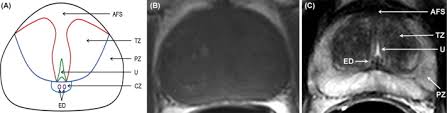

Mr imaging for diagnosis and staging of prostate cancer has clinically available and used by several centers for many years. Mri can not only confirm the presence of prostate cancer but pinpoint its location. An mri can determine whether prostate cancer has … The current diagnostic pathway for prostate cancer has resulted in overdiagnosis and consequent overtreatment as well as underdiagnosis and missed diagnoses in many … Mri is valuable in diagnosing many conditions …

The current diagnostic pathway for prostate cancer has resulted in overdiagnosis and consequent overtreatment as well as underdiagnosis and missed diagnoses in many … Mri scans can show if the cancer has spread outside the prostate … If the scan shows a problem, it can be targeted … Mr imaging for diagnosis and staging of prostate cancer has clinically available and used by several centers for many years. Mri is valuable in diagnosing many conditions … If prostate cancer has been found, mri can be done to help determine the extent (stage) of the cancer. 15.09.2021 · mri a valuable tool in early diagnosis and evaluation of the extent of tumors, such as prostate cancer. If you have a raised psa level, your doctor may refer you to hospital for an mri scan of your prostate.